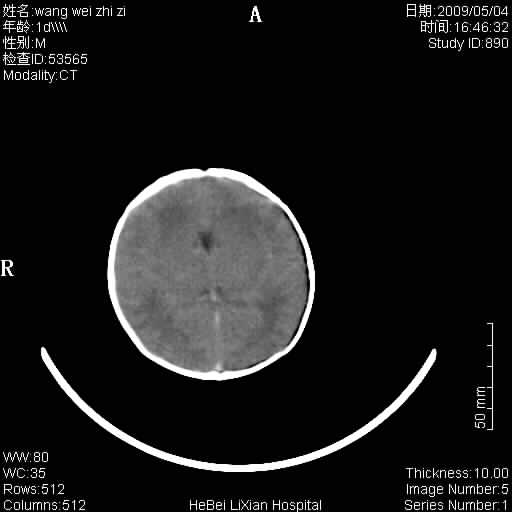

患者,男,1天,上肢抽动数次伴气促.有急产史.可以诊断珠网膜下腔出血吗?

局部5毫米薄层扫描

缺血缺氧性脑病,蛛网膜下腔出血。

此例符合缺血缺氧性脑病并蛛网膜下腔出血.